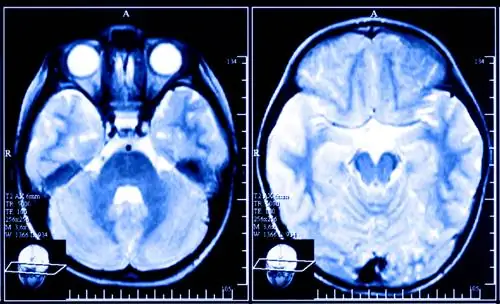

Можно создать мозговые паттерны, связанные с привязанностью и нежностью, используя нейробиоуправление, когда кто-то сканируется в аппарате функционального магнитного резонанса (фМРТ). Последнее исследование было проведено в Бразилии. «Находясь в аппарате фМРТ, испытуемых просили думать о воспоминаниях о привязанности и гордости, глядя на экран с кружком. Исследователи использовали алгоритмы обнаружения паттернов, называемые «машинами опорных векторов», для классификации паттернов в мозгу участников. Когда эти закономерности были обнаружены, круг рябил и менял форму. (Это не изменилось для контрольной группы.)»